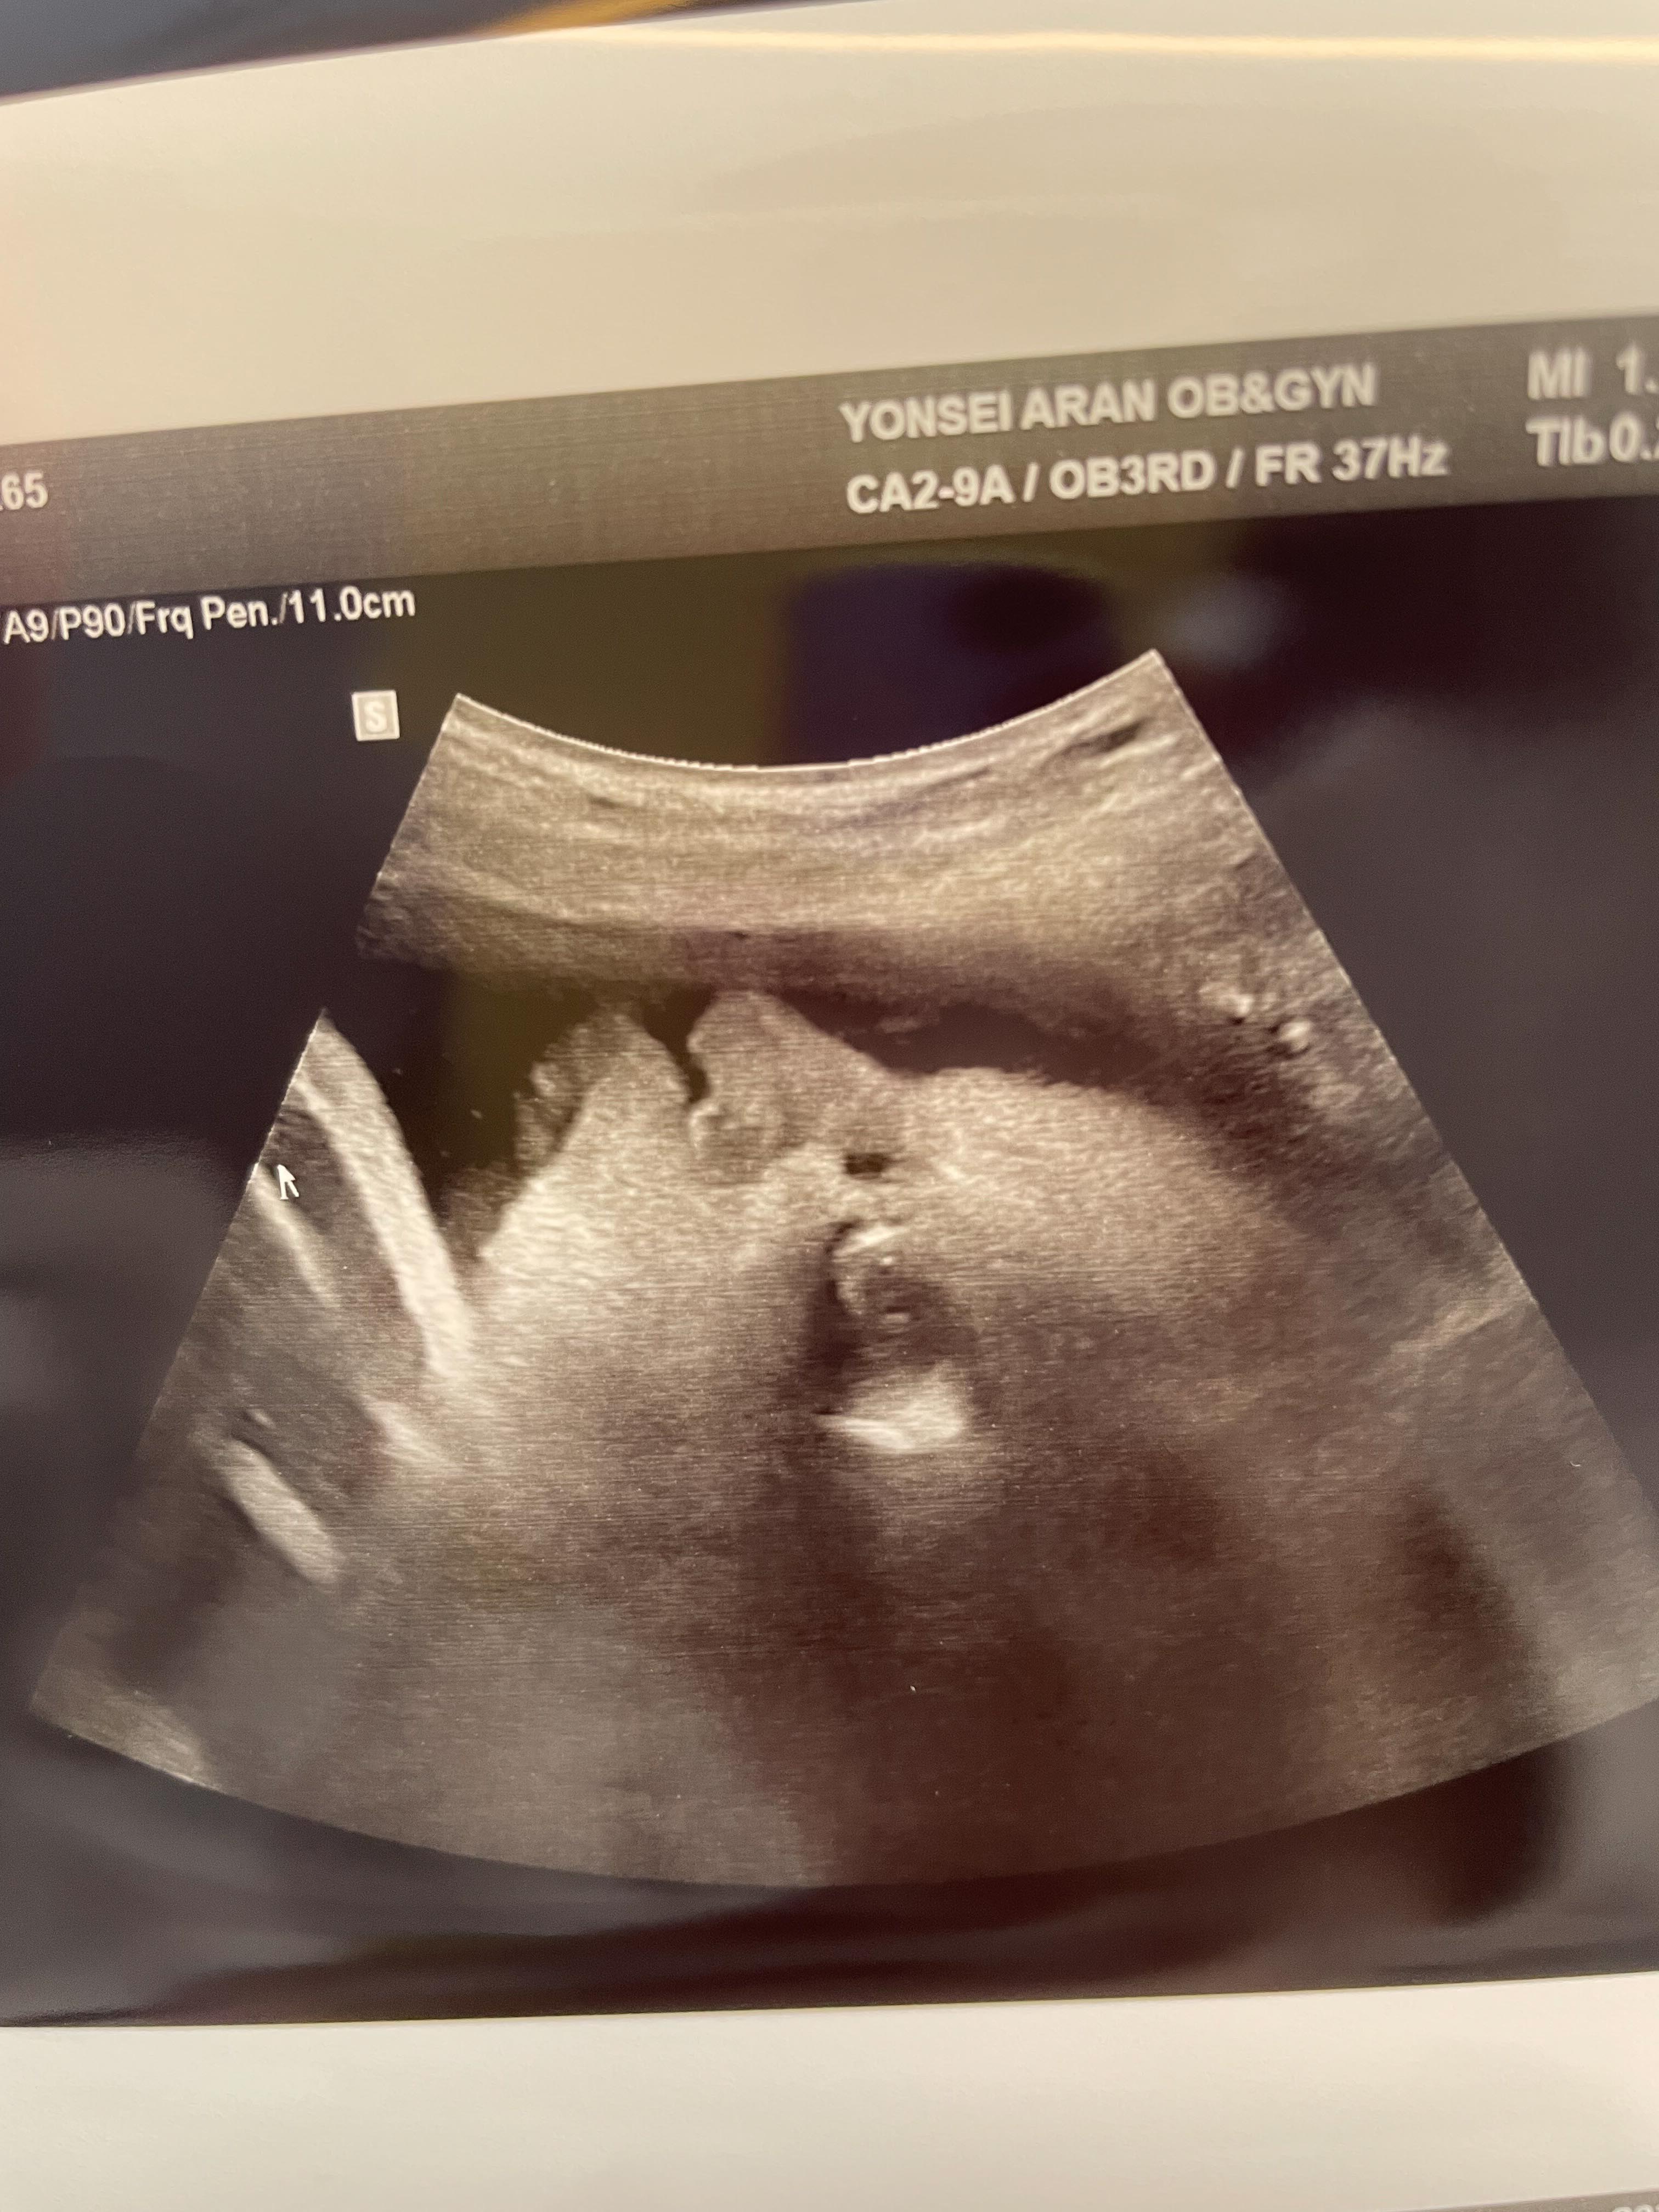

35주 1일

웬일로 얼굴을 보여줬다.

붕어와 찐빵의 콜라보 같은 느낌!

코가 남편 닮은 것 같기도..

이제 포도는 2.5kg으로 언제태어나도 정상 분만으로 볼 수 있다고 하셨다.